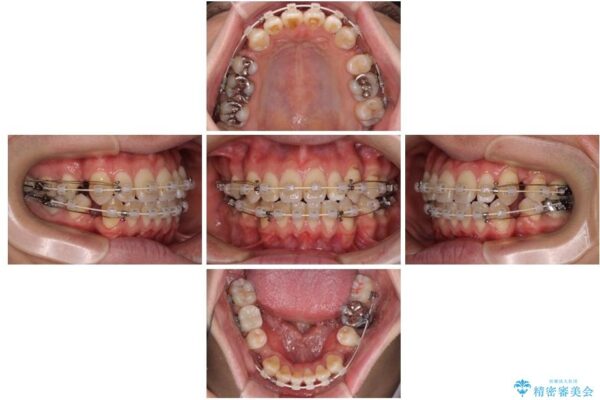

治療途中

• 口元の突出感を改善!目立ちにくいワイヤー矯正で自信を持てる自然な横顔に 治療途中画像

装置は、透明感のあるクリアブラケットとホワイトコーティングされたワイヤーを使用した、目立ちにくい審美装置を選択。

周囲に気づかれにくく、日常生活にも自然に溶け込みます。